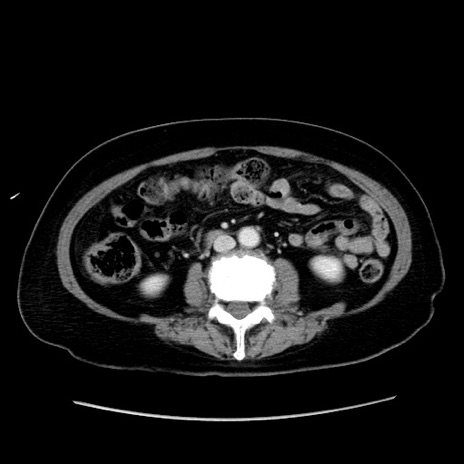

症例19(横断像)

【症例】80歳代女性

【主訴】下腹部痛

【現病歴】約8時間前より下腹部痛の出現あり、救急外来受診。

【既往歴】両側付属器切除

【身体所見】意識清明、下腹部正中に手術痕あり、その部位に一致して圧痛と反跳痛あり。腸蠕動音は亢進。

【データ】WBC 9300、CRP 0.15